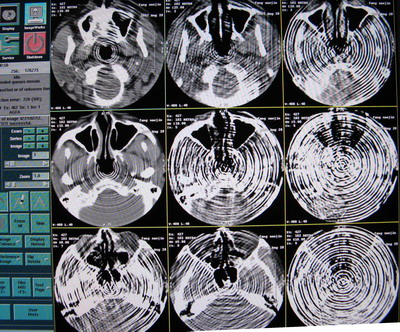

CT掃描圖像出現(xiàn)偽影,偽影圖像如下:

出現(xiàn)的頻率很高,且無(wú)規(guī)律,查看Error log,無(wú)報(bào)錯(cuò)。

6.原因會(huì)不會(huì)是數(shù)據(jù)到了 OC 這邊重建出了問(wèn)題呢,用原來(lái)正常圖像的原始數(shù)據(jù)用相同的條件進(jìn)行重建,發(fā)現(xiàn)正常圖像的原始數(shù)據(jù)重建出來(lái)的圖像出現(xiàn)了偽影,如下圖:

重建出來(lái)的偽影圖像

7.用原來(lái)掃出來(lái)不正常空氣圖像的原始數(shù)據(jù)用相同條件反復(fù)重建如下圖:

從上面幾幅圖可以看出,每次重建出來(lái)圖像出現(xiàn)偽影的地方都不同,原來(lái)不正常的圖像可以重建出正常的圖像,再次證明了原始數(shù)據(jù)是沒(méi)有問(wèn)題的。